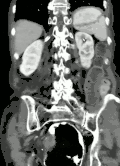

Volvulus with gangrene of the sigmoid